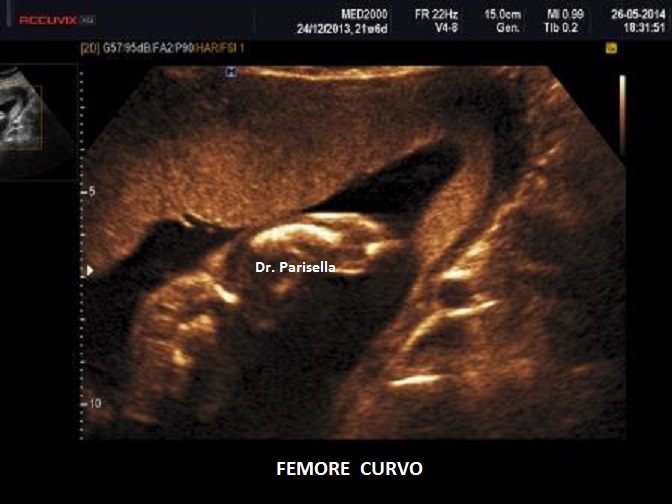

E' una patologia rara caratterizzata da craniosinostosi delle suture coronale e lambdoidea con conseguente brachicefalia, anomalie facciali ( bozze frontali prominenti, ipoplasia medio-facciale, proptosi), anomalie scheletriche (sinostosi radio-omerale, femore curvo, ulna curva, contratture articolari, campodattilia), anomalie del SNC (Idrocefalia), cardiopatie congenite (DIA), anomalie renali, anomalie dell'apparato genito-urinario (atresia vaginale, ipoplasia grandi labbra, fusione piccole labbra). I gomiti sono fissi causa la sinostosi radio-omerale.